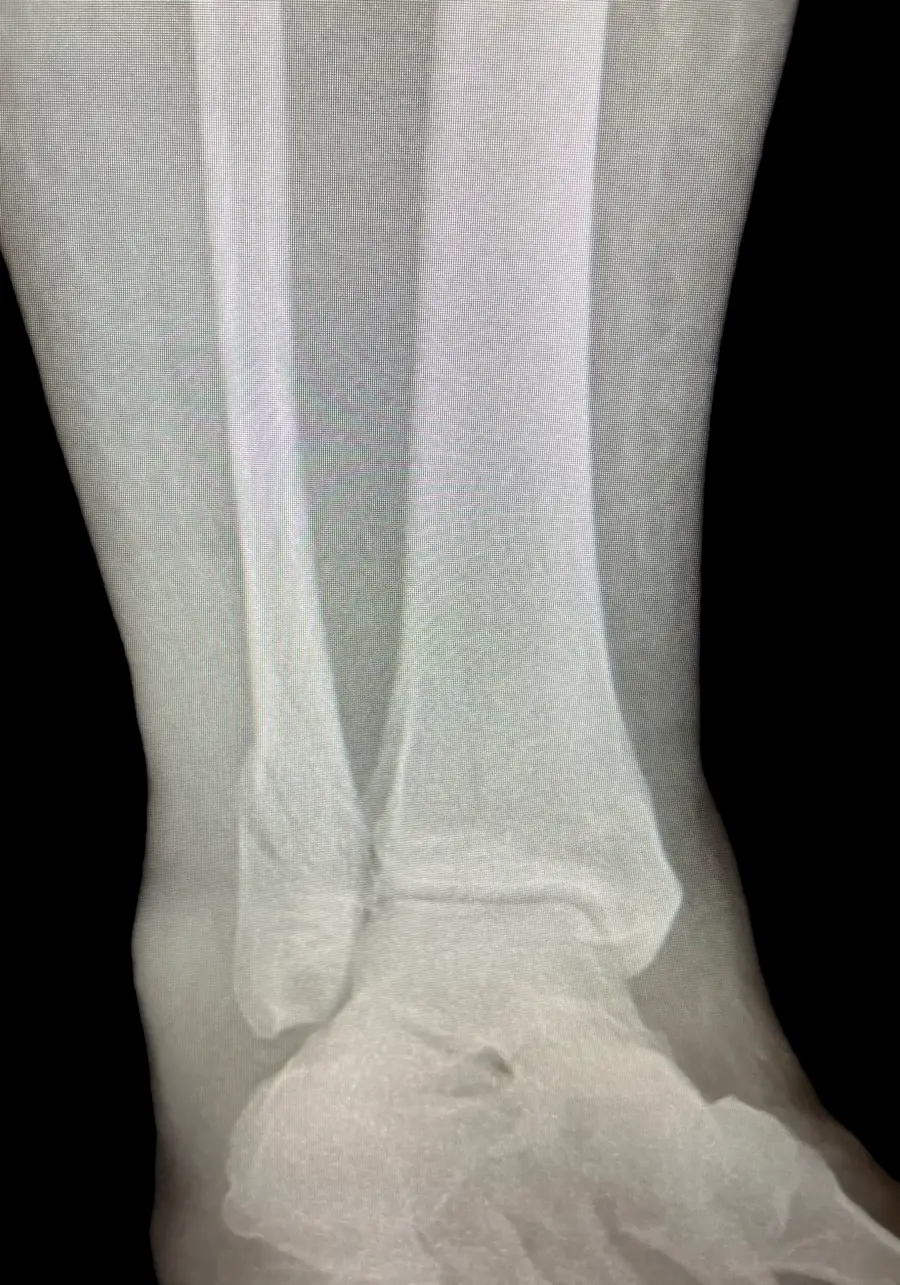

Surgical Intervention at Stepwell Institute is never a “one-size-fits-all” solution. We view surgery as a precise tool used to restore the natural biomechanics of the foot and ankle when non-invasive methods have reached their limit. Our philosophy centers on individualized surgical planning—using advanced imaging to map out the procedure before you ever enter the operating room. From correcting bunions and hammertoes to performing ligament repairs and fracture fixations, Dr. Yakov utilizes techniques designed to minimize trauma to the surrounding tissues, thereby reducing the risk of complications and ensuring a more stable, long-term result for our patients.

Identifying the Need: When Surgery is the Right Choice in NJ

Our Case Study